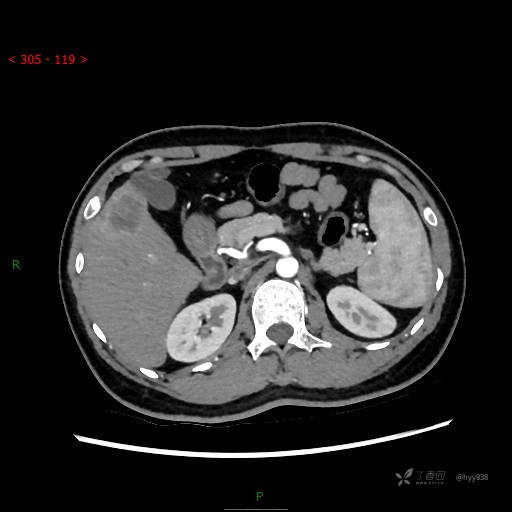

门脉期